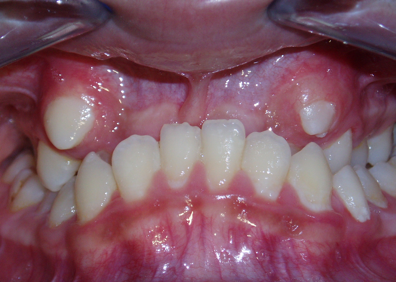

3.2.2 Alterazioni sul piano orizzontale

Nelle alterazioni sul piano trasversale i rapporti tra i molari superiori e quelli inferiori sono alterati: i molari superiori, che dovrebbero essere più esterni rispetto ai corrispondenti inferiori, spesso non lo sono. Rientra in questa categoria:

Morso incrociato

denti di un lato o di entrambi i lati combaciano in modo inverso rispetto alla norma (il molare superiore rimane più interno anziché più esterno all’inferiore). Il morso incrociato monolaterale è quasi sempre accompagnato da spostamento laterale di mandibola e mento verso il lato dell’incrocio. In tali casi è comune il sovraccarico della articolazione dello stesso lato della deviazione (il condilo viene compresso verso la cavità articolare) e una contrattura muscolare asimmetrica.

Nel morso incrociato bilaterale la simmetria può essere conservata ma l'occlusione patologica limita i movimenti funzionali della mandibola causando lo spasmo (contrazione) dei muscoli facciali.

Morso inverso

Si riscontra nelle classiche malocclusioni di III classe. In questo caso esiste uno spazio trasversale tra incisivi superiori e inferiori a causa di protrusione della mandibola (per cui gli incisi inferiori risultano anteriori ai superiori).

Anche qui risulta compromesso il sigillo labiale e la normale funzione di deglutizione e masticazione. Contrazioni e inversioni possono interessare uno o più denti fino a tutta l’arcata superiore; in questo caso, l’alterazione sul piano trasversale si associa al raggruppamento delle alterazioni del piano sagittale.